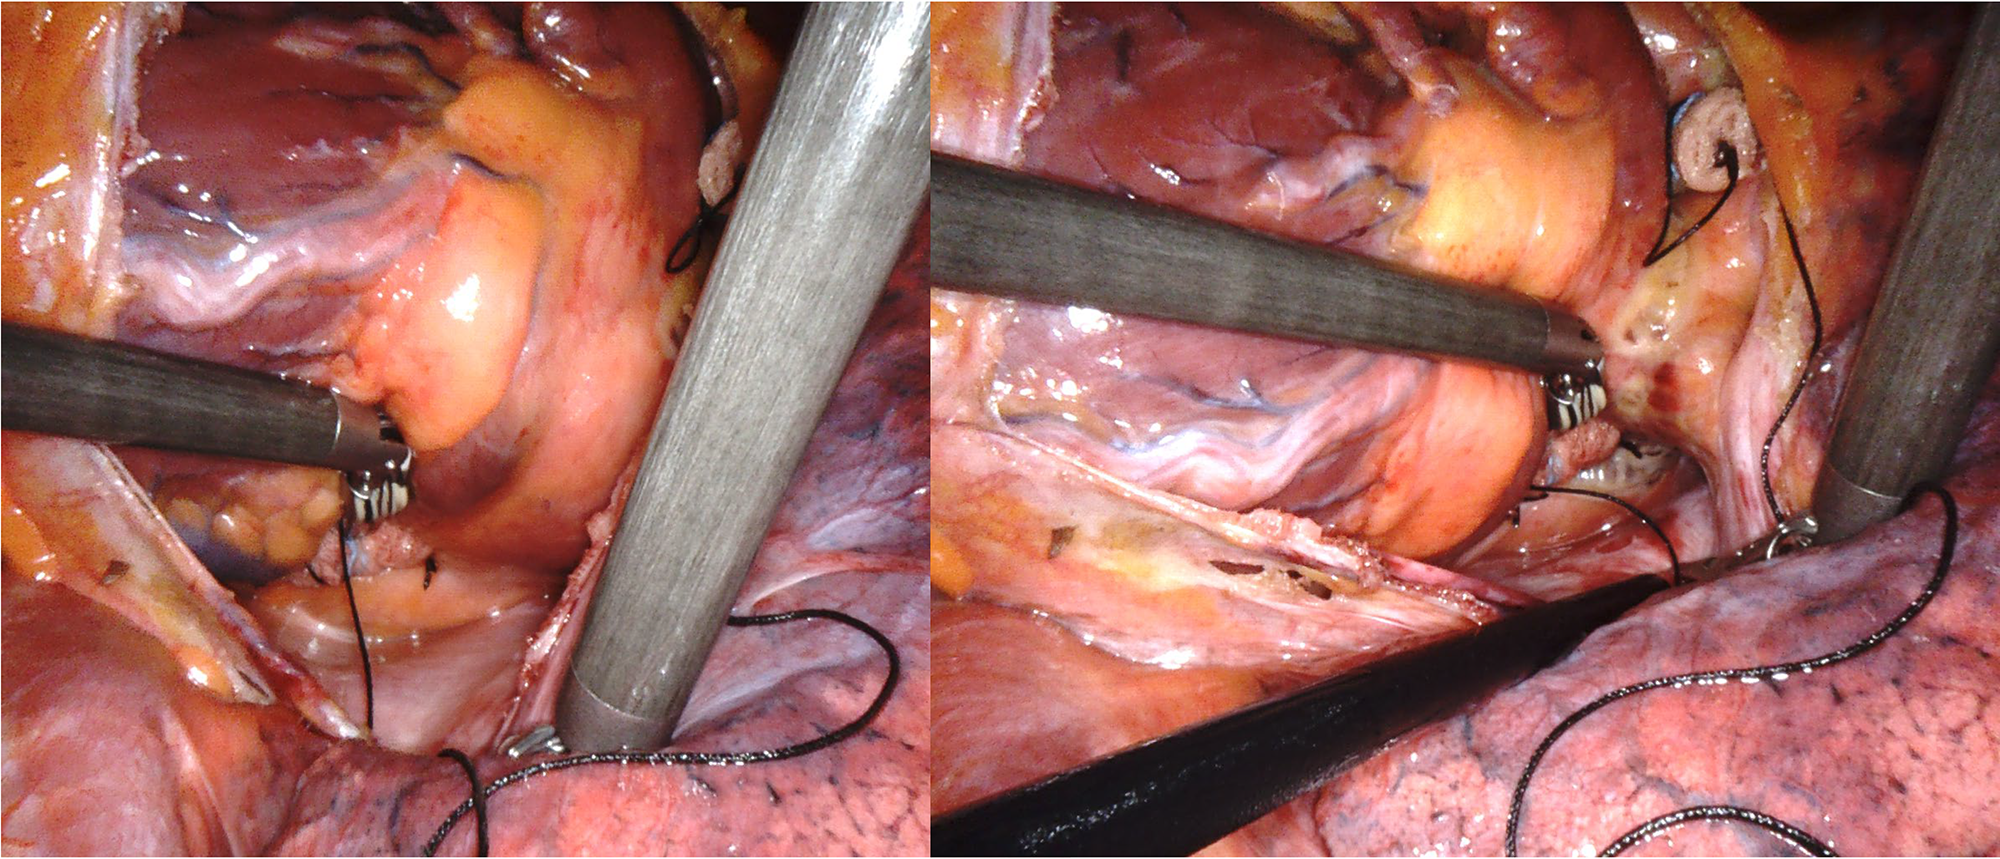

European guidelines for the management of AF define percutaneous pulmonary vein (PV) ablation as a first-line treatment within a shared decision-making rhythm control strategy in patients with paroxysmal AF, to reduce symptom, recurrence, and progression of AF [3]. However, sub-optimal outcomes of catheter ablation (CA) in patients with persistent or long-standing persistent AF have driven the pursuit of alternative methodologies. Surgical ablation represented by the Cox-Maze Technique has proven to be a safe and effective technique in sinus rhythm restoration [4]. However, the invasiveness of the procedure and higher risk of post operative complications compared with the transcatheter approach limits its use, especially to concomitant cardiac surgery. In fact, the first Cox Maze procedure required full sternotomy and cardiopulmonary bypass to perform a complete set of lesions, including both the left and right atrium and epi/endocardial ablation lines [5]. To emulate the success of the Cox-Maze procedure while minimizing invasiveness, closed-chest thoracoscopic epicardial PVI has been developed. The advent of robotic technology has further enhanced these procedures, offering improved precision by magnified visualization and dexterity optimization. These features allow precise positioning and control of the ablation probe and a better control of surrounding cardiac structures, reducing the risk of damage (Fig. 3). These characteristics also facilitated access and extended ablation beyond the PVs to the posterior wall, roof and floor of the LA and left auricle. A preliminary study of our center [2] described encouraging results of this technique in term of safety and feasibility.

Fig. 3. Intraoperative robotic vision during ablation procedure.

A cornerstone of the technique is based on its customization to the patient, which requires in-depth anatomical knowledge to avoid chest or cardiac lesions, especially during the first phase of the “learning curve” [6].